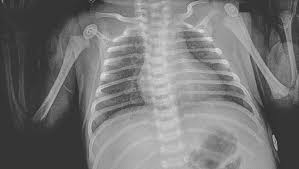

Ratselhafter Patient Baby Mit Flussigkeit In Der Lunge Der Spiegel

Kann Beim Baden Wasser In Die Lungen Meines Babys Gelangen